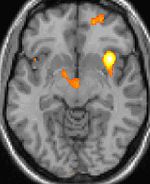

The most common type of vascular headache is migraine. Migraine headaches are usually characterized by severe pain on one or both sides of the head, an upset stomach, and, for some people, disturbed vision. It is more common in women. While vascular changes are evident during a migraine, the cause of the headache is neurologic, not vascular. After migraine, the most common type of vascular headache is the "toxic" headache produced by fever.